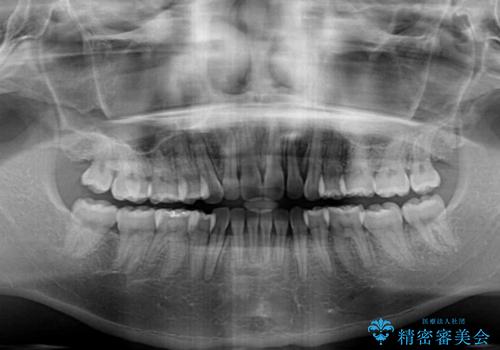

- 前歯のデコボコと口元の突出感を気にして来院された患者様です。

上下左右第一小臼歯4本を抜歯し、ワイヤー装置にて口元を引っ込めるよう矯正治療を行うこととしました。

叢生が強かったため、口元の突出感の改善には限界がありましたが、横側からも口元が引っ込んだ感じが分かるほど改善されました。